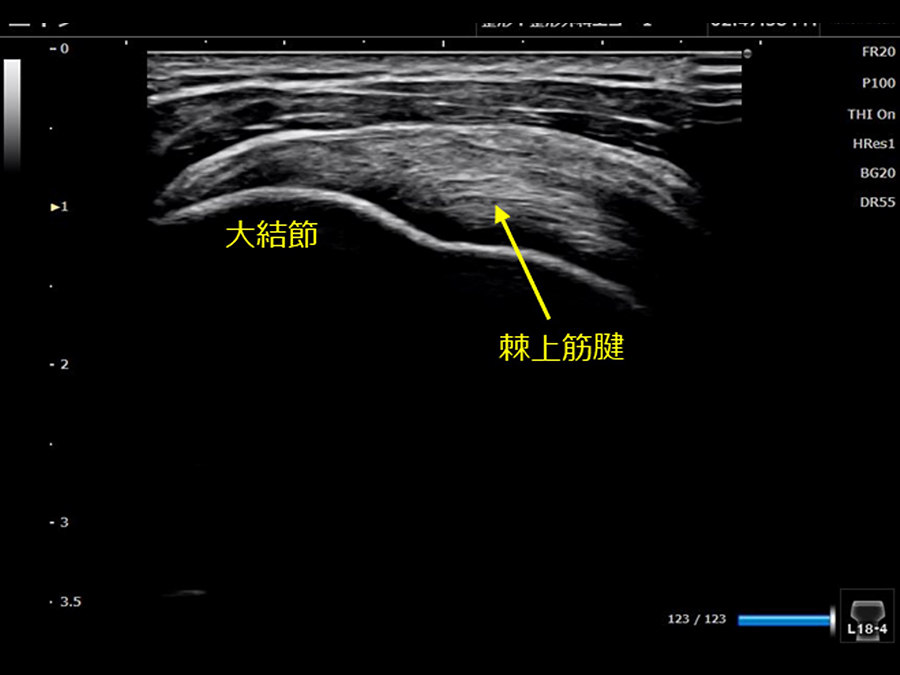

②肩のエコーチェック

超音波診断装置(エコー)を用いて肩の骨、筋・腱などを観察し、痛みにつながるような所見が無いかチェックします。

診断装置には下の画像右側の様にエコー像が記録されます。

得られるエコー画像の例